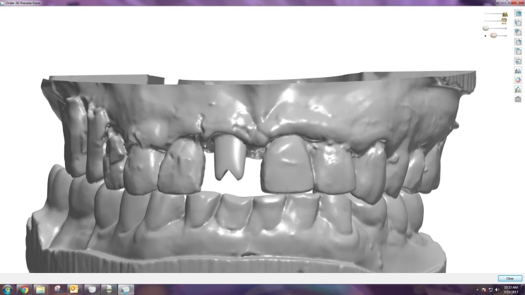

After completing an initial diagnostic appointment, a patient accepted three single-unit full-contour zirconia crowns that were milled from the digital impression and cut back for porcelain application. The application by a technician is analog dentistry. The ability of a dental laboratory to scan an analog crown-and-bridge impression is called converting an analog impression to a digital impression. The workflow after the conversion has become digitized. A dental model is virtually created with computer software, and a full crown proposal is fabricated for inspection virtually before the crown is milled (Figure 2). Due to the color of the digitized impression, the margins of the crown preparations are more easily and rapidly identified. The laboratory will also 3D print a working model, which will be used to develop the morphology of the final restoration by hand placement of porcelain (Figure 3). The decision to prescribe a full contour zirconia crown with cutback for porcelain application or complete full contour zirconia crowns lies solely on the attending dentist.9 A discussion with the patient before preparation of the teeth is imperative. After the discussion, the patient requested the zirconia copings with cutback and porcelain application for the posterior crowns (Figure 4 and Figure 5).

Fig 2. Digital impression and proposal of zirconia cutback before porcelain application.

Figure 2